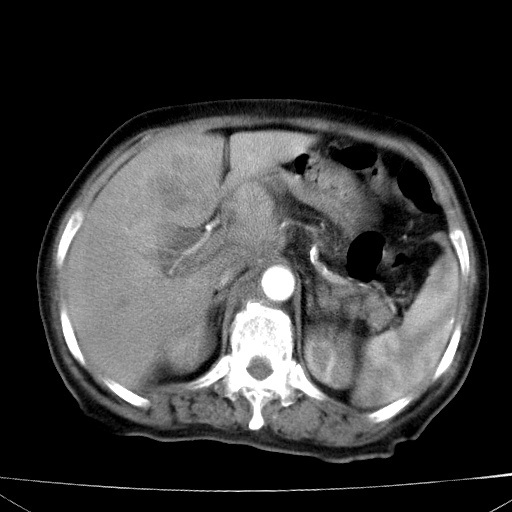

网站人气太旺!昨天的帖子就沉到海底,只好再发贴!ct18338:女 78岁,肝胆病变,已增强,再会诊!原帖链接:http://www.radida.com/bbs/forum.php?mod=viewthread&tid=50032

1)考虑胆囊癌侵犯肝脏并肝门区、腹膜后及右侧膈角后淋巴结转移。2)肝左叶近肝顶部囊肿。3)肝左叶肝内胆管结石。4)左肾近下极囊肿。

1、胆囊癌侵犯肝脏并腹腔及腹膜后淋巴结转移。

2、肝左叶外侧段囊肿。